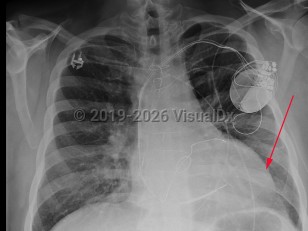

Dilated cardiomyopathy

Patients usually present with symptoms of heart failure including dyspnea, edema, orthopnea, and weight gain. Physical examination may reveal signs of acute left ventricular failure, such as S3 gallop, systolic murmur consistent with mitral regurgitation, pleural effusions, jugular venous distension, and/or peripheral edema.